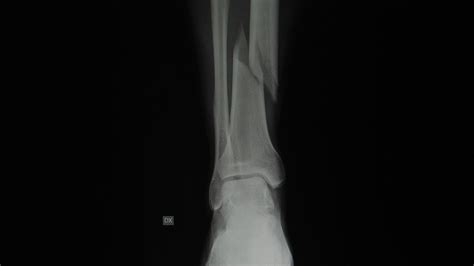

• Compound Leg Fracture

• Compound Fracture Ankle